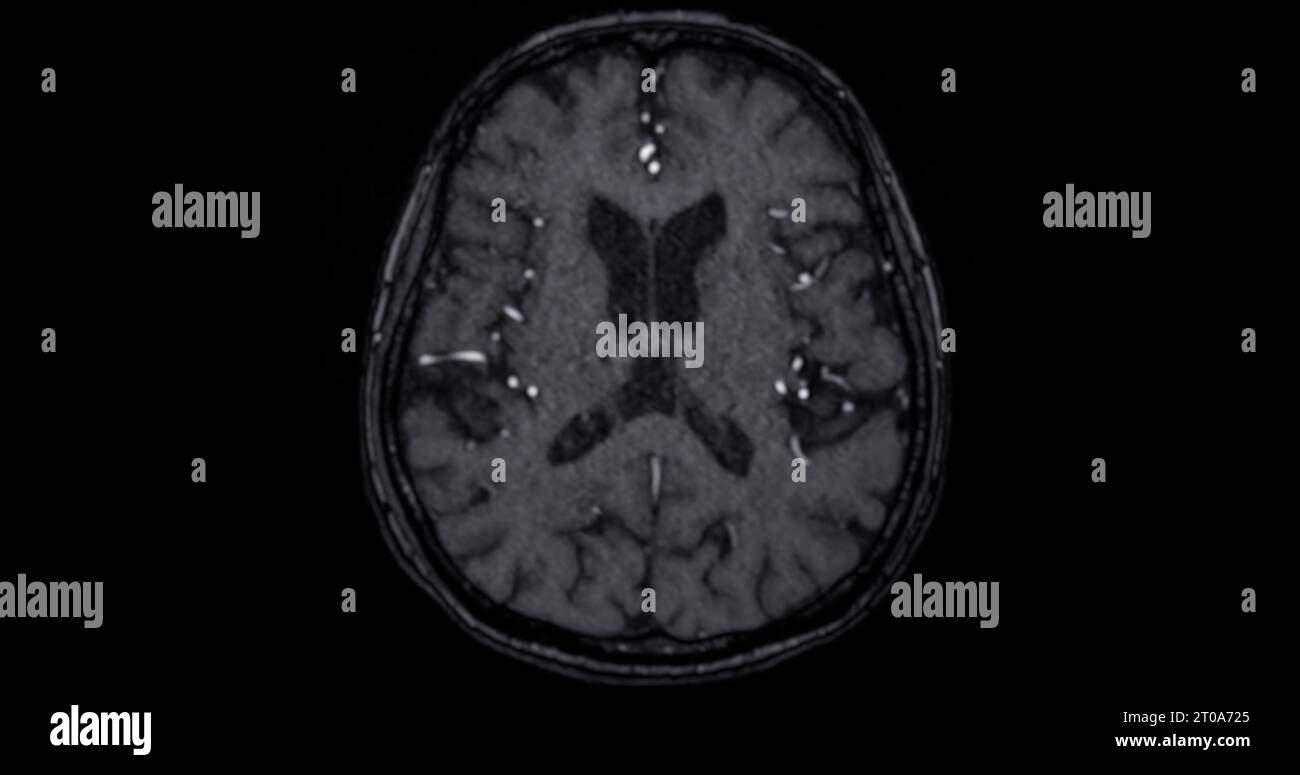

What Can Mri Scans Detect In The Brain. A variant called mr angiography. an mri of the brain can be used to evaluate many symptoms which may be caused by abnormalities in the central nervous system. mra can also be used to detect aneurysms in the brain and vascular malformations — abnormalities of blood vessels in the brain,. doctors use mri scans to diagnose and monitor head injuries and to check for abnormalities in the head or brain. mri can detect abnormalities that might be obscured by bone with other imaging methods. With the mri results in hand,. a head mri is a useful tool for detecting a number of brain conditions, including: using an mri scan, doctors can identify any bleeding or swelling in the brain and determine the extent of any damage. Aneurysms, or bulging in the blood vessels of the brain. mri is used to analyze the anatomy of the brain and to identify some pathological conditions such as cerebrovascular incidents, demyelinating.

A variant called mr angiography. Aneurysms, or bulging in the blood vessels of the brain. With the mri results in hand,. an mri of the brain can be used to evaluate many symptoms which may be caused by abnormalities in the central nervous system. mri can detect abnormalities that might be obscured by bone with other imaging methods. doctors use mri scans to diagnose and monitor head injuries and to check for abnormalities in the head or brain. mri is used to analyze the anatomy of the brain and to identify some pathological conditions such as cerebrovascular incidents, demyelinating. mra can also be used to detect aneurysms in the brain and vascular malformations — abnormalities of blood vessels in the brain,. using an mri scan, doctors can identify any bleeding or swelling in the brain and determine the extent of any damage. a head mri is a useful tool for detecting a number of brain conditions, including:

What Can Mri Scans Detect In The Brain mri is used to analyze the anatomy of the brain and to identify some pathological conditions such as cerebrovascular incidents, demyelinating. mra can also be used to detect aneurysms in the brain and vascular malformations — abnormalities of blood vessels in the brain,. mri is used to analyze the anatomy of the brain and to identify some pathological conditions such as cerebrovascular incidents, demyelinating. A variant called mr angiography. an mri of the brain can be used to evaluate many symptoms which may be caused by abnormalities in the central nervous system. using an mri scan, doctors can identify any bleeding or swelling in the brain and determine the extent of any damage. a head mri is a useful tool for detecting a number of brain conditions, including: With the mri results in hand,. doctors use mri scans to diagnose and monitor head injuries and to check for abnormalities in the head or brain. mri can detect abnormalities that might be obscured by bone with other imaging methods. Aneurysms, or bulging in the blood vessels of the brain.